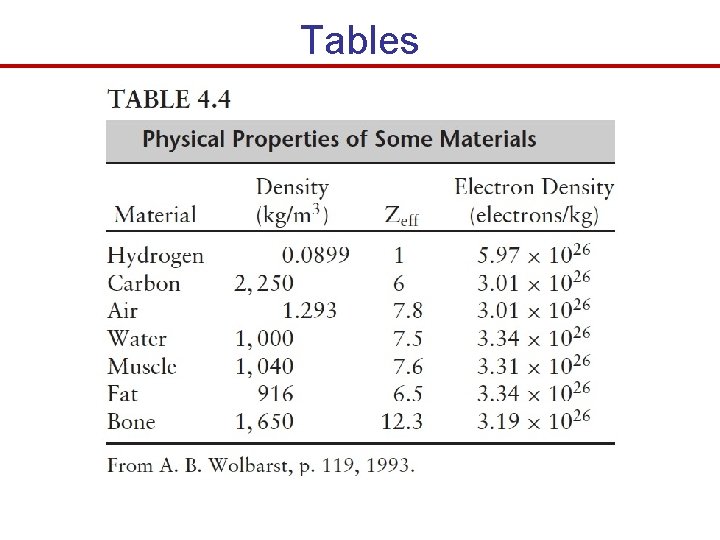

Tables